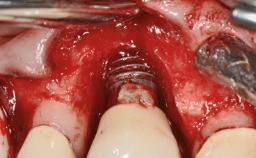

A 77-year-old male patient was referred for the management of frequent and repeated acrylic fracture of his existing mandibular fixed full-arch implant-supported metal/acrylic prosthesis. He also complained about softtissue soreness and the lack of retention and stability of his maxillary removable partial metal/acrylic prosthesis. Both prostheses had been delivered two years previously as part of his full-mouth rehabilitation (caries, tooth wear, tooth fracture). His medical history revealed high blood pressure, controlled with the use of antihypertensive medication.

- Surgical SAC classification

- Advanced